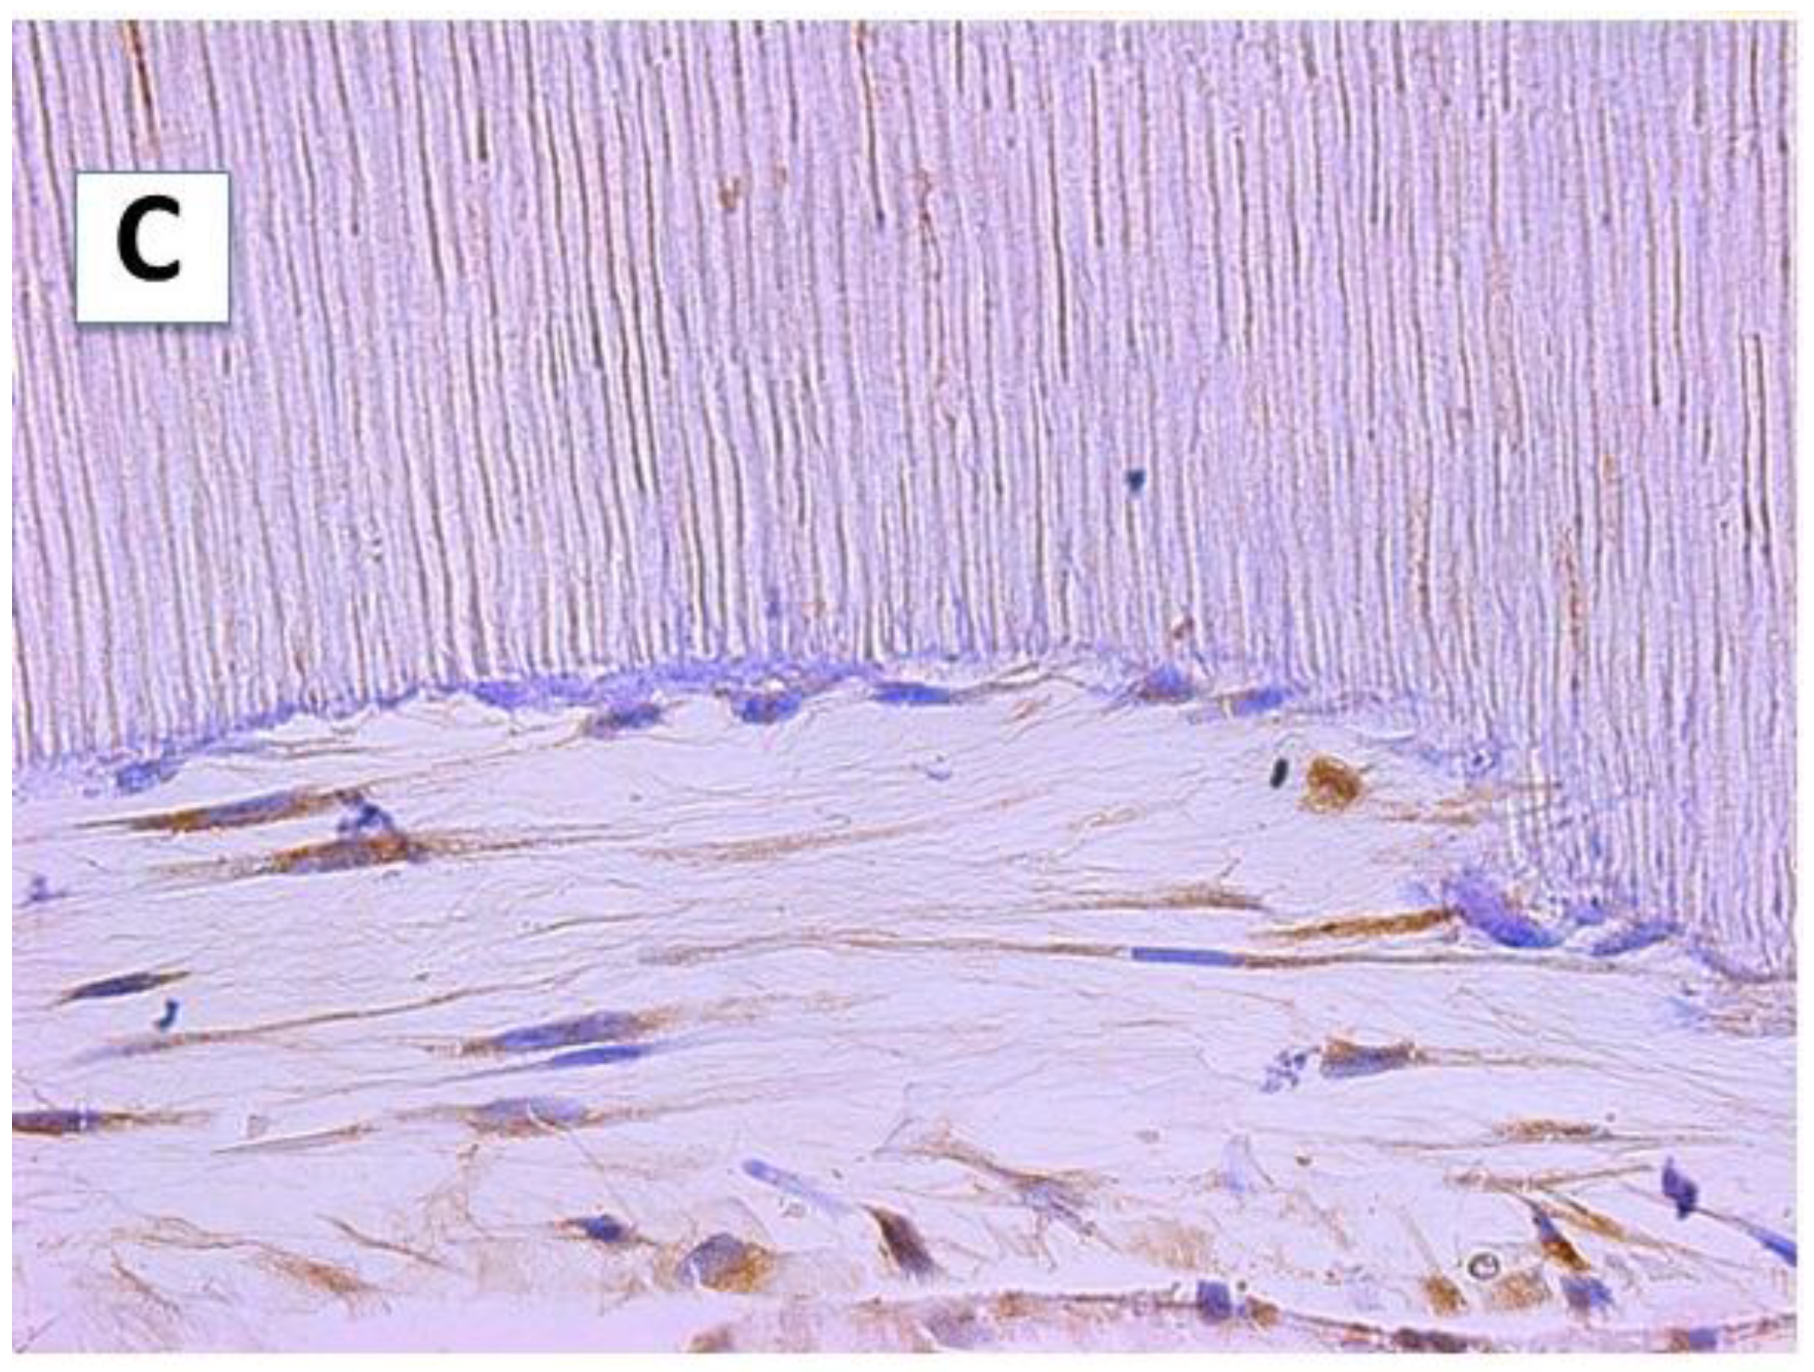

The hDPSCs actively proliferated on the cementum surface of the scaffolds. These cells synthesized abundant amounts of extracellular matrix, consisting of dense fibrous connective tissue with thick bundles of collagen fibers (Figure 3, panel A). The density of collagen fibers was higher in proximity to the cementum surface, where thick collagen fiber bundles arranged perpendicular to the cementum surface were observed (Figure 3, panel B). Some DSPP deposits were also observed, not only in the cytoplasm of these cells, but also in the newly formed matrix (Figure 3, panel C). Cells formed more cohesive layers than on surface A, with a denser extracellular matrix and visible DSPP deposits.

Figure 3.

The hDPSCs were cultured on the surface B (SB) of the scaffold for 6 weeks and processed by light microscopy. (A): Collagen fibers (arrow) oriented perpendicular to the SB (Masson’s trichrome staining, 40×). (B): The hDPSCs formed flattened cell layers, which produced a matrix rich in collagen fibers (arrows) that were preferentially arranged perpendicular to the tooth root surface. Hematoxylin–eosin staining (100×). (C): An immunohistochemical study of DSPP protein showed intracellular deposits of DSPP in the hDPSCs and in the newly synthesized intercellular matrix (40×).

On this surface, the hDPSCs acquired a flattened morphology, forming well-organized layers of 3–6 cells surrounded by a newly formed extracellular matrix. The extracellular matrix that was located between the cell layers was looser than that located on the cementum surface (Figure 3, panel A).